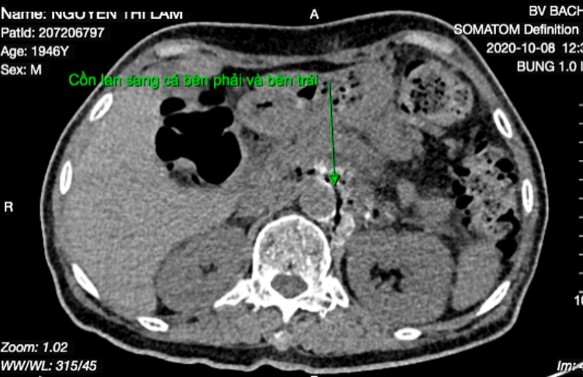

Bơm cồn tuyệt đối lan quanh động mạch chủ bụng